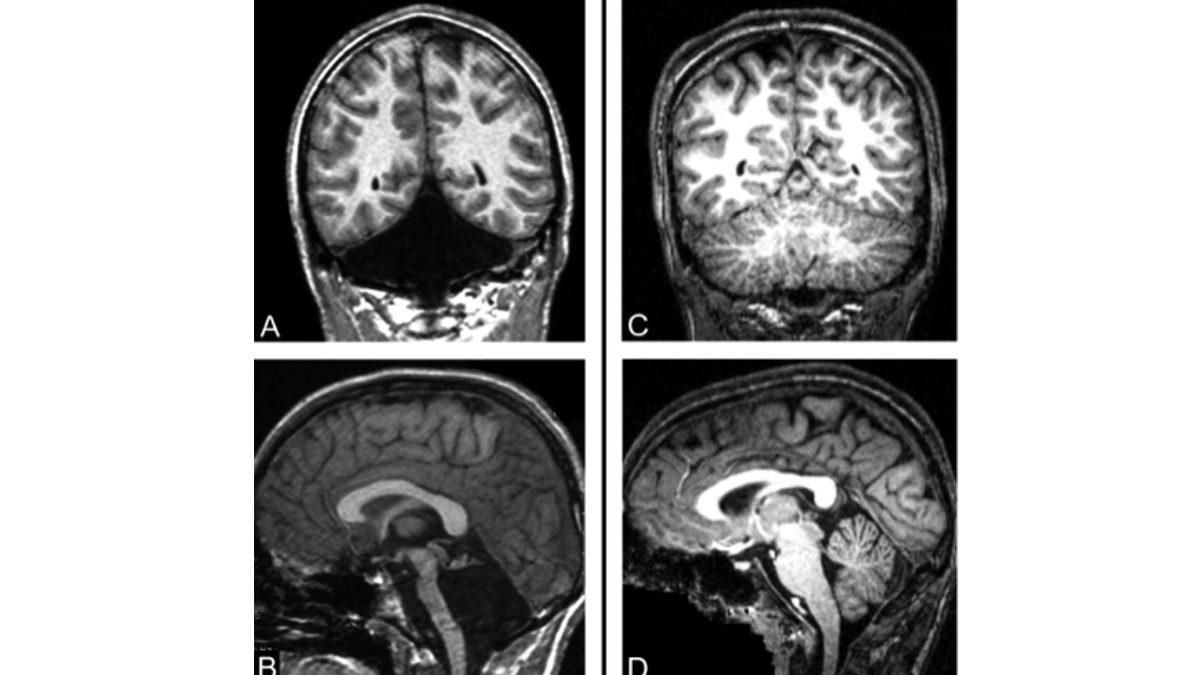

Jonathan henüz bebeklik çağlarında, bir bebeğin belli bir gelişime ulaştığında kendi kendine yapabilmesi gereken oturmak, yürümek ve koşmak gibi temel becerileri yerine getiremiyordu. Bu durumdan şüphelenen ailesi, oğullarını birçok doktora götürmeye başladı. Sonunda 5 yaşındayken yapılan bir beyin taraması, neyin ters gittiğini ortaya çıkardı.

Jonathan, bir beyinciği olmadan doğmuştu ve beyinciğinin olması gereken yerde siyah bir boşluk vardı.

Mide bulantısı ve baş dönmesi şikayetleriyle doktora giden ve bu rahatsızlıklar ışığında tetkikleri yapılan kadının, 2014’te doktorlar tarafından beyinciğinin olmadığı ve bu organ yerine o bölgenin beyin omurilik sıvısıyla dolu olduğu tespit edildi.